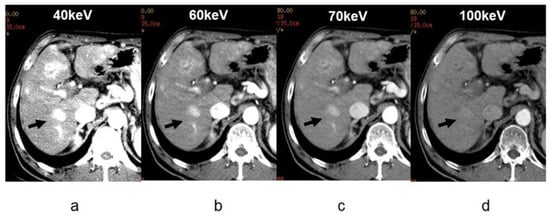

3.1. Virtual Monochromatic Imaging

- Yamada, Y.; Jinzaki, M.; Tanami, Y.; Abe, T.; Kuribayashi, S. Virtual monochromatic spectral imaging for the evaluation of hypovascular hepatic metastases: The optimal monochromatic level with fast kilovoltage switching dual-energy computed tomography. Investig. Radiol. 2012, 47, 292–298. [Google Scholar] [CrossRef]

- Caruso, D.; De Cecco, C.N.; Schoepf, U.J.; Schaefer, A.R.; Leland, P.W.; Johnson, D.; Laghi, A.; Hardie, A.D. Can dual-energy computed tomography improve visualization of hypoenhancing liver lesions in portal venous phase? Assessment of advanced image-based virtual monoenergetic images. Clin. Imaging 2017, 41, 118–124. [Google Scholar] [CrossRef]

- Lv, P.; Lin, X.Z.; Chen, K.; Gao, J. Spectral CT in patients with small HCC: Investigation of image quality and diagnostic accuracy. Eur. Radiol. 2012, 22, 2117–2124. [Google Scholar] [CrossRef]